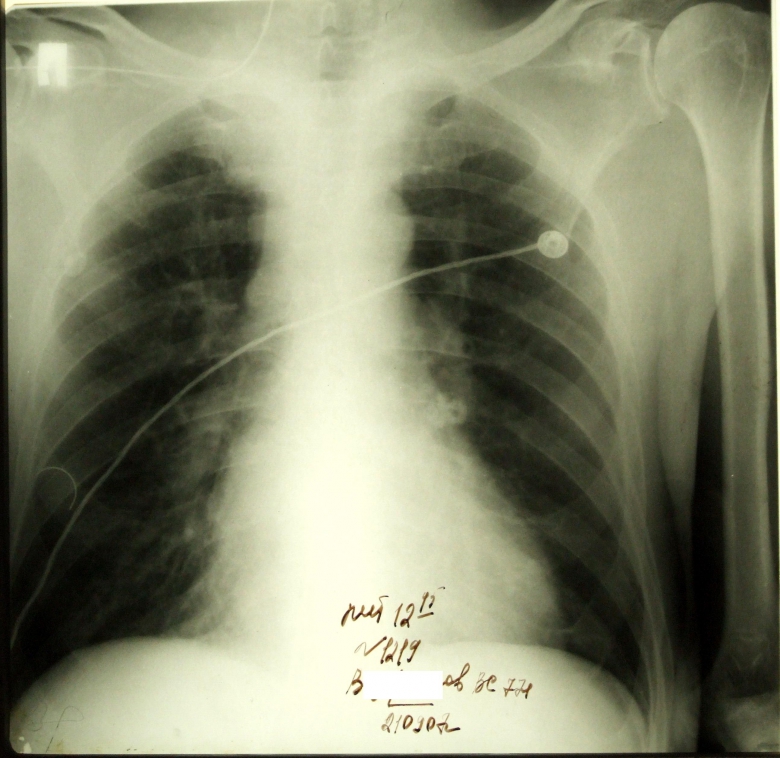

Электрод причем никак не хотел идти вниз. Видимо интрадюссер сразу попал в яремную

Обсуждалось здесь viewtopic.php?f=24&t=1606